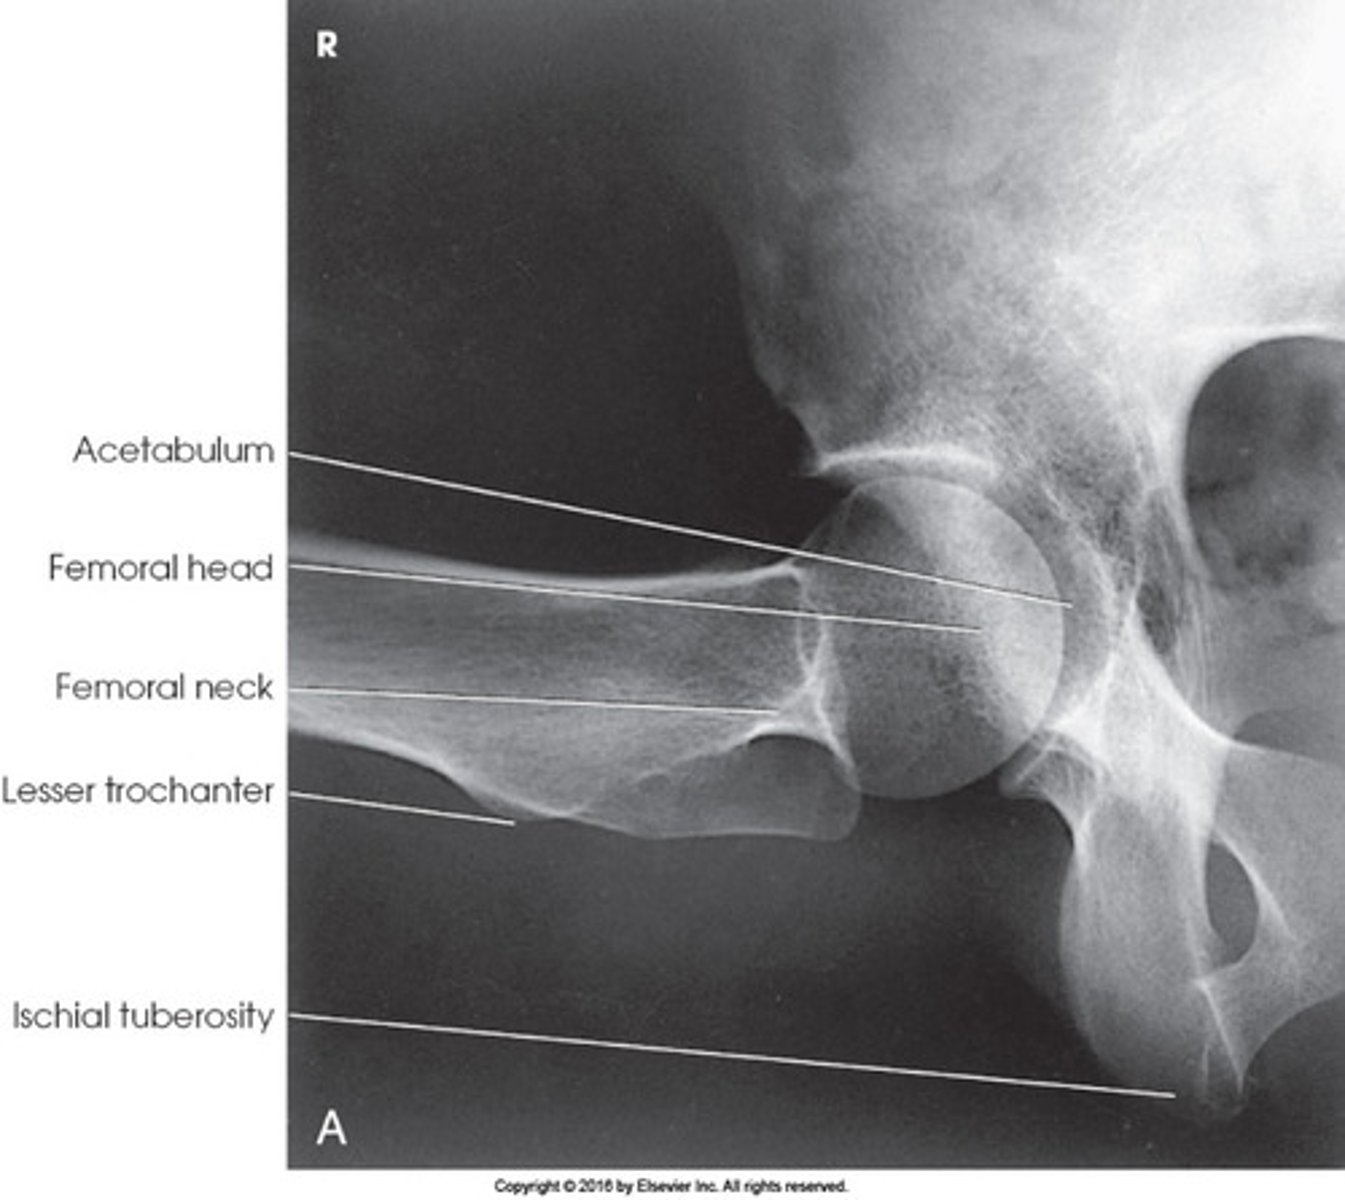

What positioning error is evident in the image below?

The lower limbs were not internally rotated

Which projection of the hip is shown in the figure above?

Axiolateral

What anatomy is labeled as letter A in the image below?

Acetabulum

IA Positioning: Axiolateral Hip

- femoral neck seen without overlap of the greater trochanter

- ischial tuberosity seen below the femoral head

- soft tissue of unaffected thigh without overlap of AOI

- small amount of lesser trochanter visible on posterior side

- small amount of greater trochanter visible on anterior and posterior portions of femur